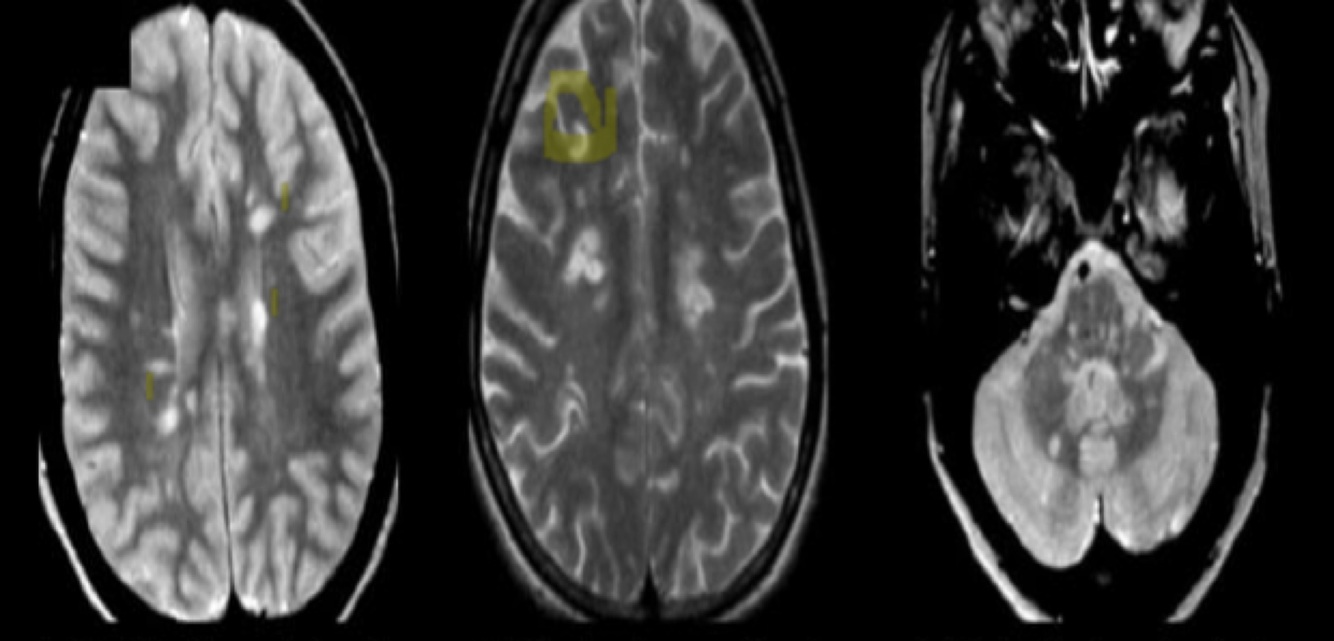

Diagnose

what do you see